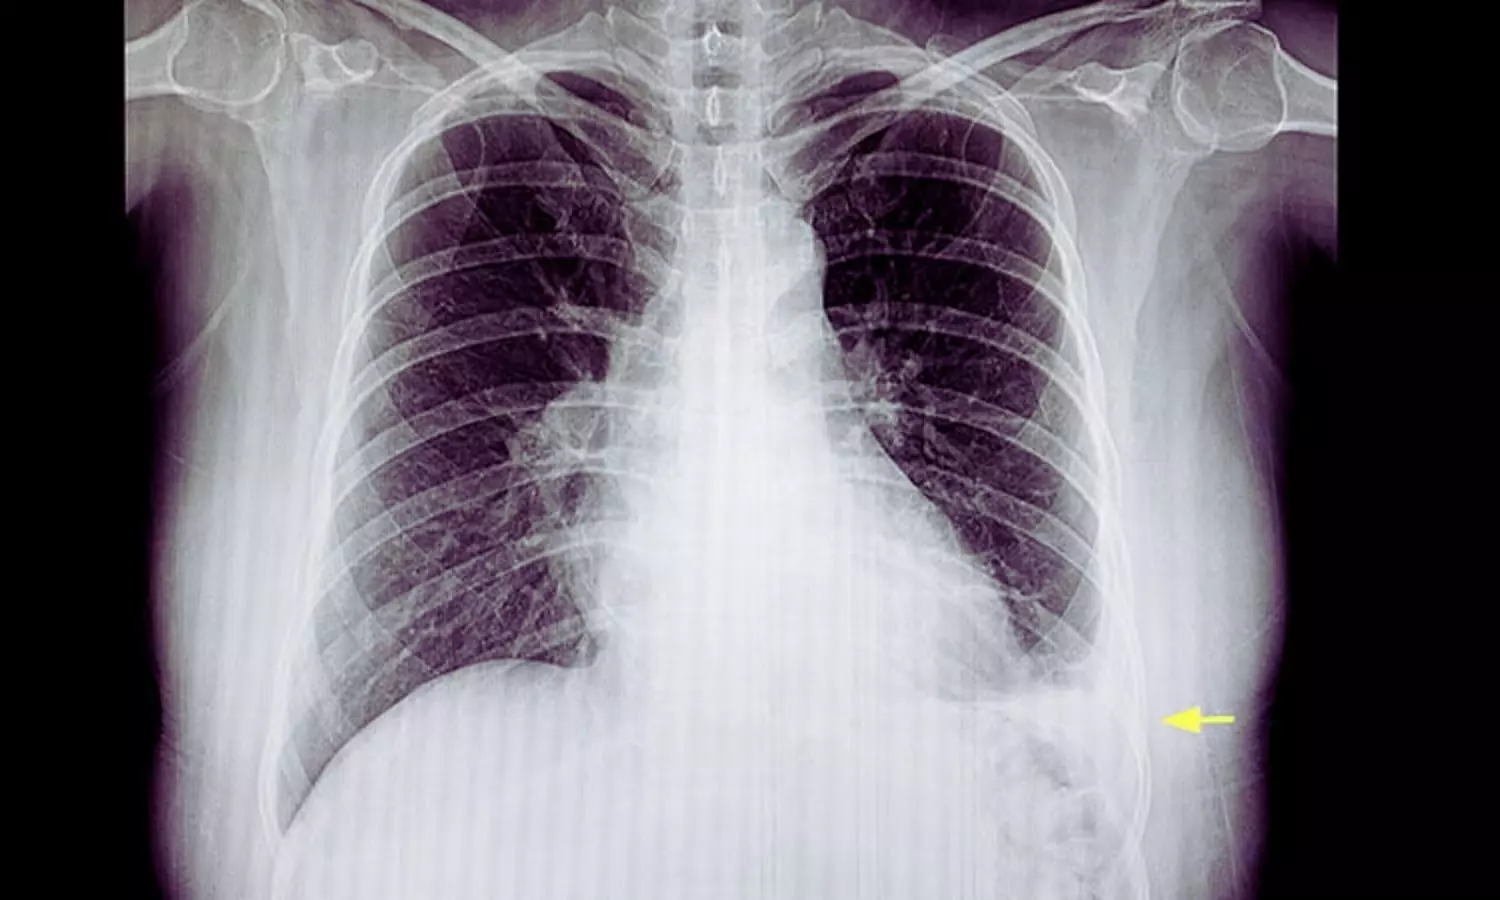

Spain: A study published in the European Respiratory Journal reports that saline lavage alone may prolong pleural drainage in patients with pleural Infection compared with intrapleural enzyme therapy (IET). The findings also indicate that adding saline lavage to IET does not provide a meaningful clinical advantage over enzyme therapy alone.Pleural infection, including complicated parapneumonic effusion and Empyema, often requires chest tube drainage along with antibiotic therapy. Intrapleural enzyme therapy—commonly involving fibrinolytics and DNase—is frequently used to enhance fluid drainage by breaking down fibrinous septations and reducing fluid viscosity. However, the clinical value of saline lavage, either as a standalone treatment or combined with enzyme therapy, has remained unclear.To investigate this, researchers led by José M. Porcel from the Pleural Medicine and Clinical Ultrasound Unit at Arnau de Vilanova University Hospital in Lleida, Spain, conducted the SCOPE trial, a randomized superiority study. The trial aimed to determine whether saline lavage alone or in combination with enzyme therapy was superior to standard IET in adults with pleural infection.The two-center prospective study included 89 patients with pleural infection, with a median age of 62 years; 73% were men. Participants were randomly assigned to one of three treatment groups: saline lavage alone (30 patients), saline lavage combined with IET (30 patients), or IET alone (29 patients). The enzyme therapy regimen consisted of once-daily intrapleural administration of 100,000 units of urokinase and 10 mg of DNase.All patients also received broad-spectrum empiric antibiotics—most commonly amoxicillin-clavulanate—initially given intravenously and later switched to oral therapy once fever resolved. Antibiotic treatment lasted at least two weeks and could be extended depending on clinical response.The primary outcome was the duration of pleural drainage, measured from randomization until chest tube removal. Secondary outcomes included radiographic reduction of pleural effusion on days two and five, length of hospital stay, and mortality or adverse events within 90 days. Key Findings:Saline lavage alone was associated with a longer pleural drainage duration compared with enzyme-based treatment.The median drainage duration was 4 days in the saline-only group versus 3 days in both the intrapleural enzyme therapy (IET) alone and saline-plus-IET groups.No significant difference in drainage duration was observed between the two IET-containing regimens.Early radiographic improvement was similar across all treatment groups.By day 2, all groups showed a median reduction of about 30% in pleural effusion size.By day 5, patients receiving enzyme therapy demonstrated greater pleural fluid resolution, with a median residual effusion of zero.Serious adverse events were uncommon during the study.One patient in the combination therapy group developed hemothorax requiring video-assisted thoracoscopic surgery.Three-month mortality rates and the length of hospital stay were comparable across all treatment groups.The researchers concluded that intrapleural enzyme therapy remains the preferred treatment approach for pleural infection. The findings do not support the routine use of saline lavage unless fibrinolytic therapy is contraindicated.Reference:DOI: https://doi.org/10.1183/13993003.01715-2025